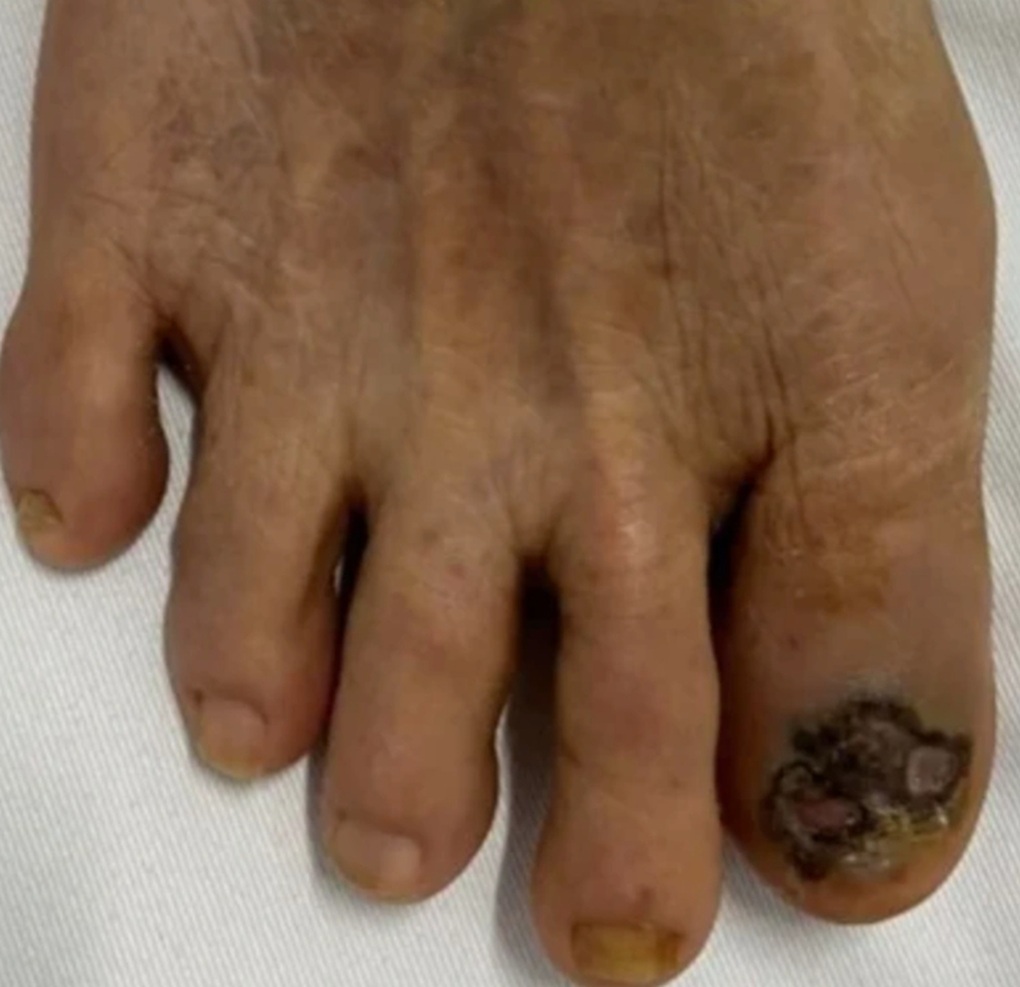

Ung thư tế bào hắc tố móng ngón cái bàn chân (Ảnh: Bác sĩ cung cấp).

Ngoài ra, thể ung thư tế bào hắc tố ở dưới móng, biểu hiện bằng các thương tổn tăng sắc tố không đều, chiếm một phần hay toàn bộ nền của móng cũng hay gặp.

Ung thư tế bào hắc tố dưới móng thường chẩn đoán muộn vì dễ nhầm với các bệnh khác như nốt ruồi dưới móng, xuất huyết do sang chấn, viêm quanh móng, nhiễm nấm, hạt cơm dưới móng.

Do vậy, với bất kỳ một thương tổn tăng sắc tố dưới móng, phải được khám kỹ, nhất là với những thương tổn lan hết chiều dài của móng.